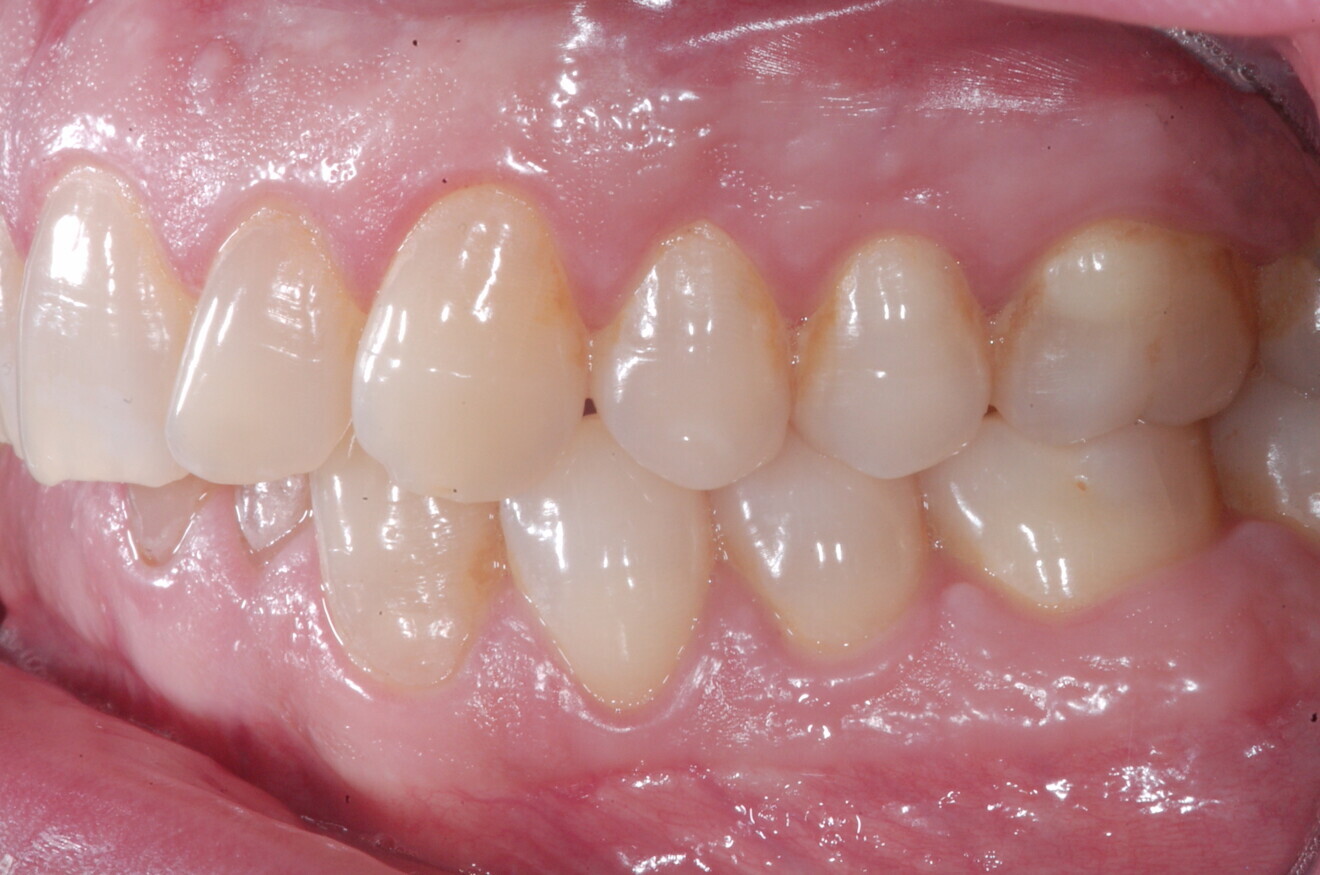

At the end of the treatment, Class I canine and molar relationships were obtained, maxillary incisor inclination was slightly increased (Ui–FH = 112°), mandibular incisor inclination (IMPA = 97.09°) was fully corrected by means of proclination and the divergency was slightly increased (SN–GoGn = 27°) because of the relative posterior extrusion and use of Class II elastics—a small variation (1°), which is interesting considering the age of the patient (Figs. 25–35). A balanced smile arc was obtained with an ideal relationship between the maxillary incisors and lower lip, and torque control of the lateral and posterior segments generated a broader smile.

At the one-year follow-up in retention (Vivera retainers with bite ramps, Align Technology), the result was stable and intercuspation was improved (Figs. 38–42).